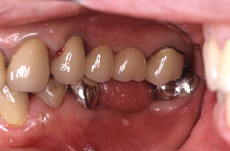

●症例1

術前

向かって右の一番奥の歯は根が折れていたので抜歯しました。

術後

奥歯に3本のセラミックの歯がセットできました。